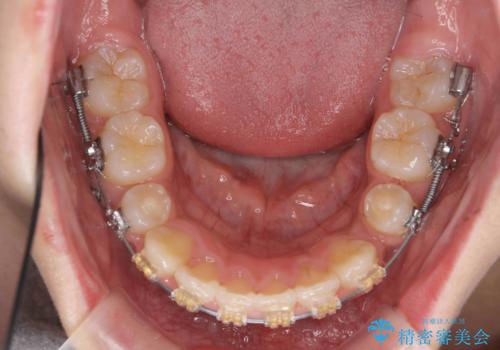

- 矯正装置

- プラスチック装置

神経の治療を先に行い、ワイヤー矯正を行いました。

上下の小臼歯を抜歯しています。

- 治療中は違和感や痛みが起こることがあります

- 症状により、抜歯が必要な場合があります

- 治療中は歯磨きがしにくくなるため、虫歯や歯周病になりやすくなります